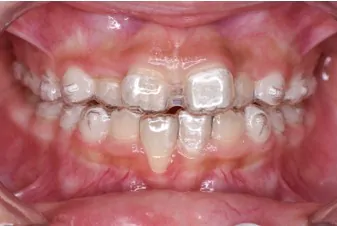

インビザライン・ファーストで対応できる症例

Before

使用中

After

症例の概要

全部で20枚のマウスピースを、1日16時間以上使用していただき、1枚を5日で交換していただき、約3ヶ月でここまで改善しました。

改善したのは前歯の噛み合わせと、奥歯が狭かったので、アーチを広げる事で永久歯が生えるスペースを作りました。

この後は永久歯の生え方等の経過を見ながら、必要に応じてマウスピースを作製し(インビザライン・ファーストは矯正開始から3年間無料で作製できます)歯並びを改善していきます。